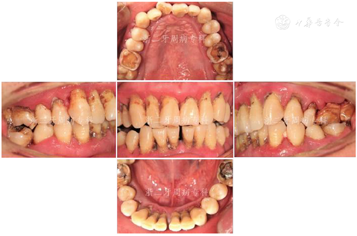

口腔卫生欠佳,软垢指数:2;牙石指数:3;全口牙龈充血红肿;平均牙周探诊深度(PD)7.0 mm,PD≥7 mm的位点占所有检查位点的63.3%(114/180),其中17颊侧远中、17舌侧远中、34舌侧远中、36颊侧近中、46舌侧近中PD深达12 mm;平均附着丧失(CAL)9.3 mm、CAL≥5 mm的位点数为98.3%(177/180);BOP(+)%:100%;37、46松动度Ⅲ度,11~17、21、22、24~27、32、34、41~43、45、47松动Ⅱ~Ⅲ度,余牙松动度Ⅰ度;36、46Ⅲ度根分叉病变。16、26、36、46牙釉质发育不Ⅲ全,11扭转,37缺失舌向倾斜,12、14~16、24、25、41、42咬合时出现异常动度,31、41可见1.5 mm左右牙间隙(图1,图2)。牙髓活力测定:17、34牙髓活力正常,36、37、46"40"无反应。

全口曲面体层X片示:全口牙槽骨广泛性水平吸收,46牙槽骨吸收超过根尖;36根尖周和根分叉区低密度影;13、22、23、33~35、43~45、47牙槽骨吸收达根长1/2~2/3,余牙牙槽骨吸收至近根尖(图3)。